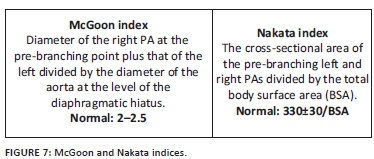

Cardiac CTA, with its multi-planar and three-dimensional reconstruction capabilities, allows accurate depiction of pulmonary artery anatomy, MAPCAs and the aorta at the level of the diaphragm. These features allow calculation of the McGoon index and the Nakata index (Figure 7) to quantitate the degree of pulmonary artery hypoplasia. The McGoon index is the preferred index in our institution and is used post-palliation (central shunt, classic or modified Blalock-Taussig shunt, Brock procedure or stent) to guide definitive repair and VSD closure when it exceeds 1.6-1.8.